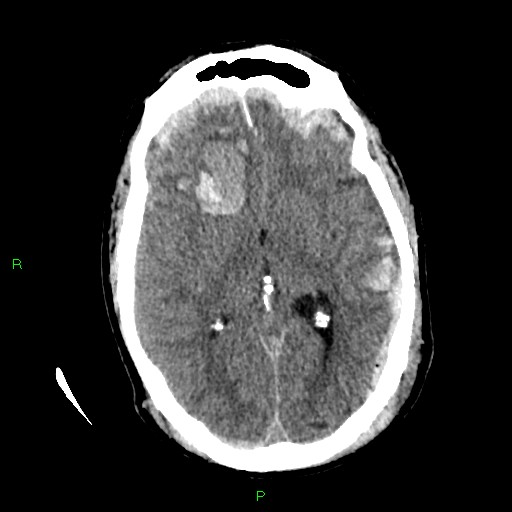

Consultant Radiologist Nick Carter joins us again to take us through interpretation of the head CT in the context of trauma. Starting with typical injuries and the patterns they show, features to aid pattern recognition and the key features on images that help guide and empower us to make the early referral to neurosurgery.

Images courtesy of Dr Derek Smith, Radiopaedia.org from the case rID: 36667, Case courtesy of Assoc Prof Frank Gaillard, Radiopaedia.org. From the case rID: 19252